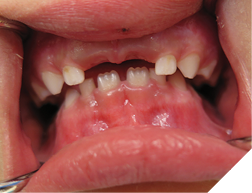

ECC occurs in young children who are fed nocturnally on demand with a fermentable carbohydrate, typically milk. Night-time feeding, whether by bottle or breast feeding, before the eruption of the maxillary incisors is not problematic. Taking a baby bottle during the day, no matter how frequently, does not seem to cause this problem. Feeding a child with a baby bottle before going to sleep is also not problematic. This may be due to the self-cleaning action of the salivary flow during the daytime. With EEC there is reduced salivary flow at night, so the substates are not washed away, but stay on the surface of the teeth. The substances in the bottle also have an effect. The more carbohydrates, the more virulent the decay. A sweetened drink such as apple juice is worse than milk, which is worse than natural breast milk. The substate stays on the tooth surface all night and is replenished regularly by repeated feedings. Why are the maxillary incisors so severely decayed, while the mandibular incisors are virtually immune with ECC? The mandibular incisors are largely unaffected due to the position of the child’s tongue while feeding. As the child sucks on the bottle, the tongue covers and protects the mandibular incisors. The primary incisors when newly erupted are not yet fully calcified and may explain why the decay progresses so quickly. The maxillary first molars may be involved but the maxillary cuspids are usually not involved as they erupt later. The second molars of both jaws may be involved if the child is still night feeding after they erupt. It may be difficult to determine if the teeth are painful, especially if the child is colicky. A good sign that the teeth are painful is that the child is not biting with their front teeth, and yet they have no other teeth. You should note that if the decay of the teeth is extensive and the teeth are infected, with draining fistulas, there may not be any pain (Fig. 1). The treatment depends at what stage you catch the disease. In the very early stages, before cavitation or incipient lesion stages, you can institute preventive measures, such as good oral hygiene with a fluoridated toothpaste and regular topical fluoride applications. However, for these recommendations to work, the night feeding must stop. Incipient lesions will appear as white frosty areas of decalcification lesions on the buccal surfaces of the teeth (Fig. 2).

Fig. 2

One treatment modality that is effective with incipient decay of this nature is professionally applied Silver Diamine Fluoride (SDF). SDF can help to arrest or slow down the progression of the lesions. One side effect that parents need to be warned about is black staining. It is important to discuss this before the treatment because it may introduce a real esthetic concern. If the teeth are extensively decayed, and with draining fistulas, the only treatment may be extraction of effected teeth (Fig. 3). If the teeth have cavitated lesions, then restorative options can be given. This usually involves an extensive treatment plan with sedation, typically a general anaesthetic (GA). For the very young, treatment should only be caried out at a hospital for safety reasons. Restoring the teeth will give the child a full functioning dentition and let the jaws develop properly. The ideal restoration for gross decay from ECC is a full coverage crown. The best being zirconium crowns (Fig. 4) or stainless steel with plastic white facings. Since the work is done under GA, the best and strongest treatment options should be considered. This will help to prevent further treatments due to failure that could involve subsequent sedations.